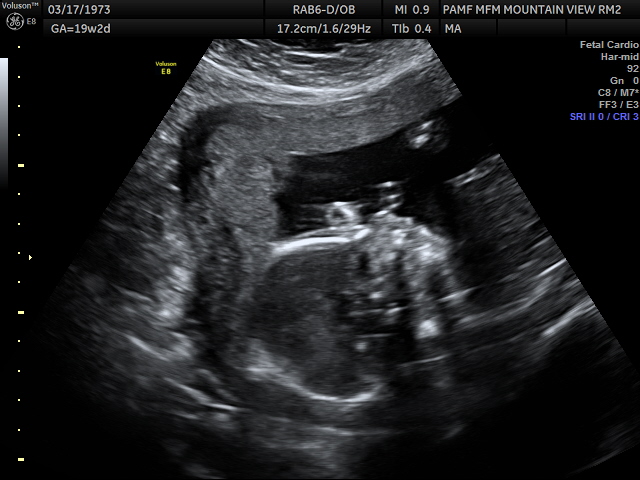

It was really great seeing the images although a lot of times I didn’t know what was on the screen, like this example.